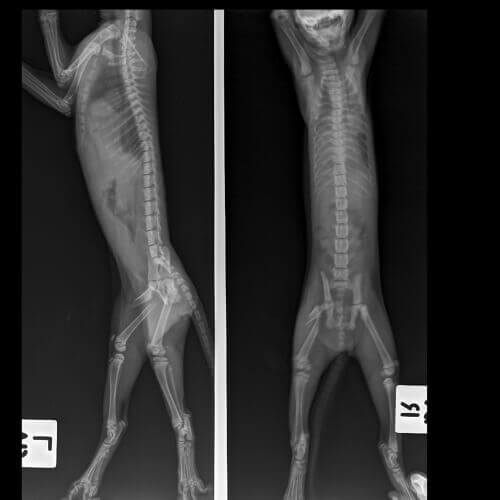

- Radiografie.

La diagnosi di gatti zoppicanti può richiedere esami specifici. Accade spesso che tra questi siano comprese una o più delle seguenti analisi: